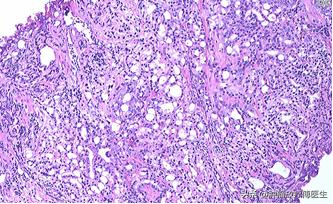

2015年10月29日我院泌尿外科行经尿道前列腺电切术,术后病理示前列腺腺泡腺癌,Gleason评分5+4=9。术后恢复可,期间出现全身酸痛,2015年11月17日查骨ECT示全身多发骨(颅骨、脊柱、骨盆、双侧肋骨、胸骨、双侧肩胛骨、左侧肱骨、双侧股骨)放射性异常浓聚。2015年11月27日行盆腔MRI报告:前列腺外周叶及中央叶多发结节样异常信号,结合病史,考虑前列腺癌。行胸、腰椎MRI平扫+增强:胸、腰椎体、双侧髂骨及所见双侧股骨多发结节状异常信号影,考虑转移灶。

2015-10-30经尿道前列腺电切术后病理